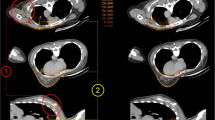

The dose distributions obtained with the different irradiation modalities are illustrated in Fig. 1 for a representative patient. The results indicate that a comparable and good coverage of the target volume is obtained independently of the radiotherapy technique or patient setup. The better conformity of PT is evident, as well as the significantly lower dose bath out-of-field compared to 3D-CRT and even more to VMAT. The OAR doses obtained with the different techniques are summarized in Table 1. As expected, the data indicate that OARs receive overall lower dose for Group 1, when SVC nodes only are included in the target. In this case, tangential 3D-CRT delivers a dose about 3 times higher than PT to the ipsilateral lung, while comparable doses below 1 Gy are obtained for the contralateral organs. Compared to Group 1, the PT dose to the ipsilateral lung increases by a factor 2.5–2.8 in Group 2 due to IMNs involvement, with a low dependence on patient setup (either FB or DIBH irradiation). Concerning photon irradiation, a dose about twice as high is observed for VMAT compared to PT. Remarkable differences between PT and VMAT are observed for contralateral OARs: while an average dose well below 1 Gy is delivered by PT, VMAT results in average doses of about 6–7 Gy and 5 Gy for the contralateral lung and breast, respectively, with a minor dependence on FB or DIBH. The dosimetric outcomes are further evidenced by the average cumulative DVHs reported in Fig. 2 for both treatment groups (the corresponding differential DVHs are reported in Additional file 1: Supplementary Figure S1).

Summary of the dose distributions obtained with the different irradiation techniques. A representative Group 1 patient receiving PT is shown in a, while the corresponding 3D-CRT plan is displayed in b. Concerning Group 2, a typical dose distribution with FB treatment is shown for PT (c) and VMAT (d). The corresponding DIBH plan is finally reported for PT (e) and VMAT (f). The limited dependence on patient setup (FB vs DIBH) can be appreciated